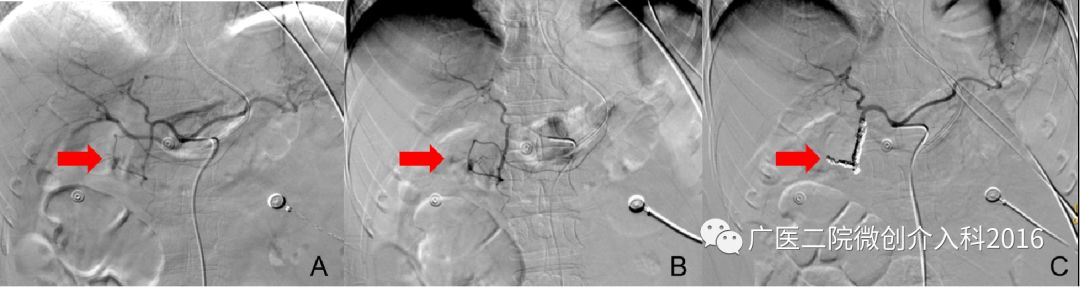

患者为十二指肠溃疡并大出血,经内科药物治疗效果不佳,仍有大量出血,生命垂危。图A、B行十二指肠动脉造影,可见造影剂浓聚和外渗,精准找到出血部位和责任血管。通过注入弹簧圈堵塞出血血管,图C再次造影可见原出血征象消失,患者出血停止。经后续治疗,患者脱离生命危险。

病例3:胆道出血

患者为经皮胆道取石术后胆道出血,经内科药物治疗无效,仍有大量出血。图A行肝动脉造影,右肝可见造影剂外溢并呈囊状扩张,表示正在出血。图B行介入栓塞治疗,注入不同规格的弹簧圈行出血动脉栓塞术。图C再次造影可见原出血征象消失,患者胆道出血停止。